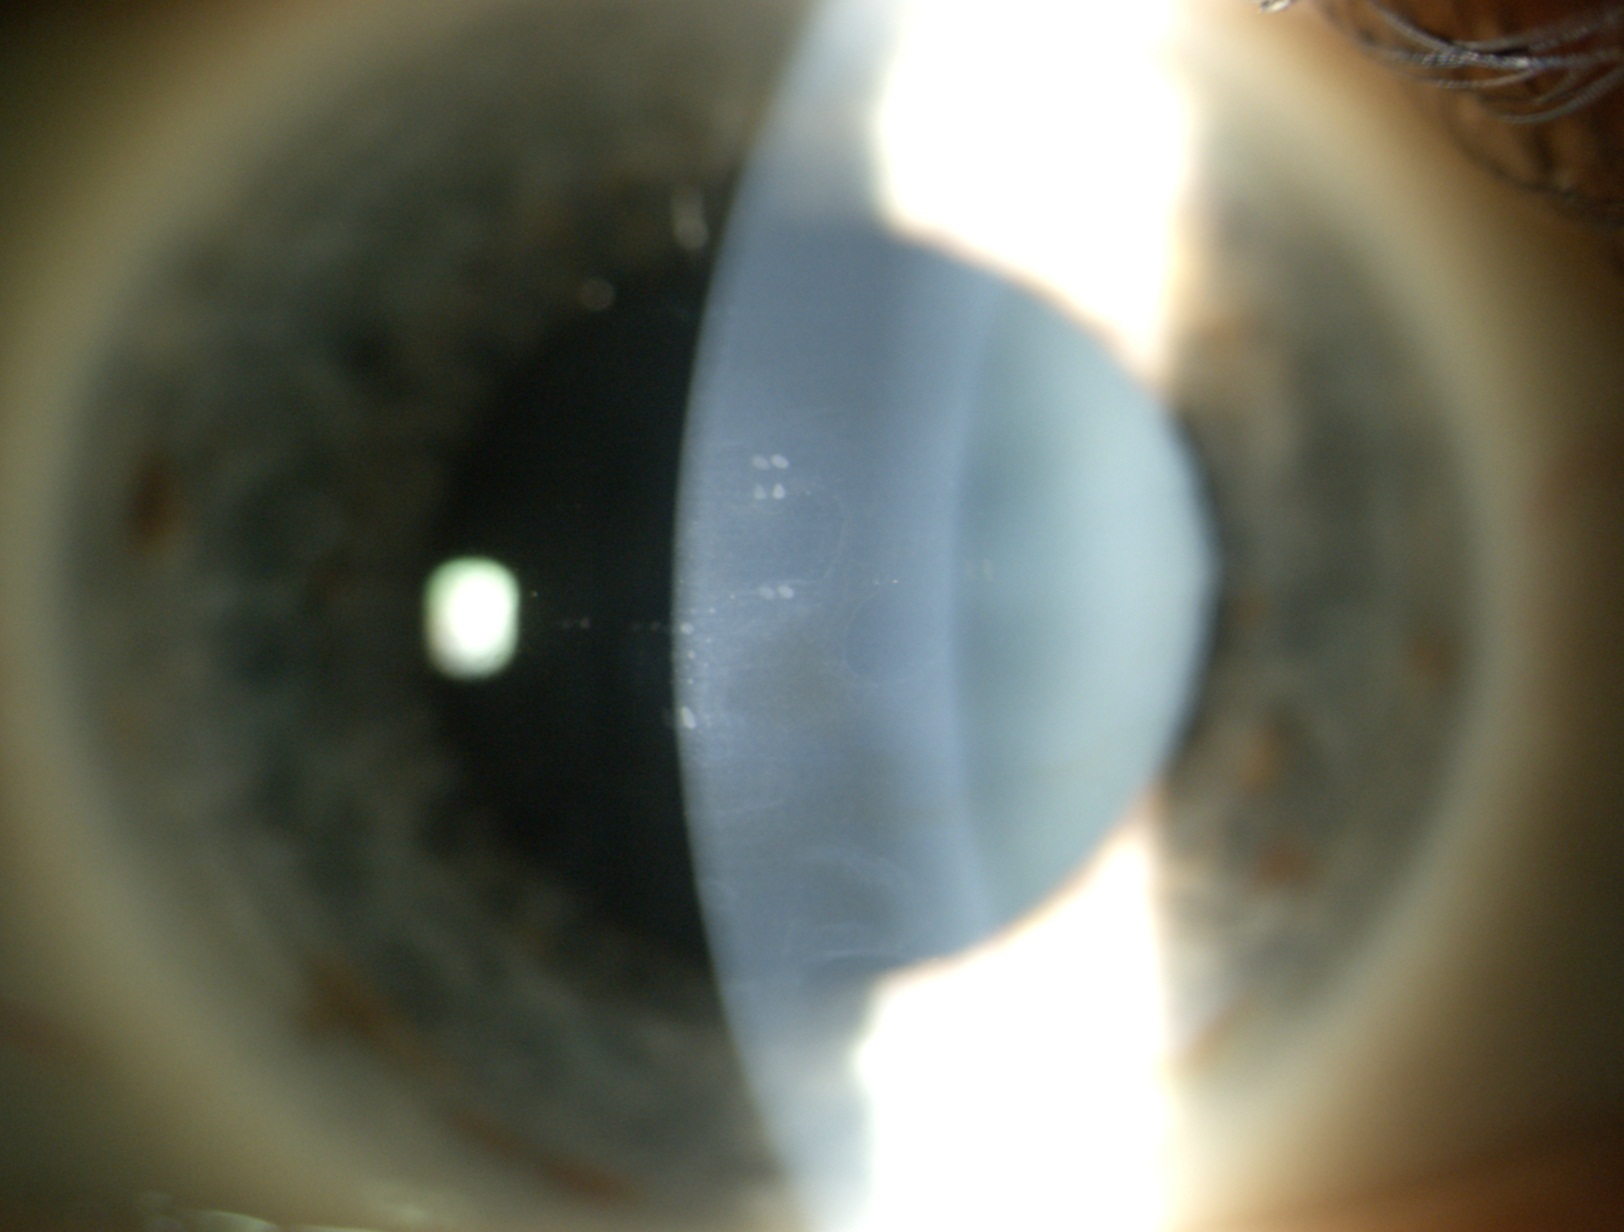

4 CHED (distrofia endoteliale ereditaria congenita)

Paziente di 16 anni con visus <1/10 cc (vecchi referti di visite oculistiche con visus di 5/10) peggiorato negli anni. Cornea opalescente di spessore molto aumentato (1100 micron circa). Posta diagnosi di CHED (distrofia endoteliale ereditaria congenita) con successivo trapianto endoteliale (DSAEK) in maggio 2011 in od.

Attualmente la cornea nell’occhio destro è trasparente e il visus è di 5/10 cc.